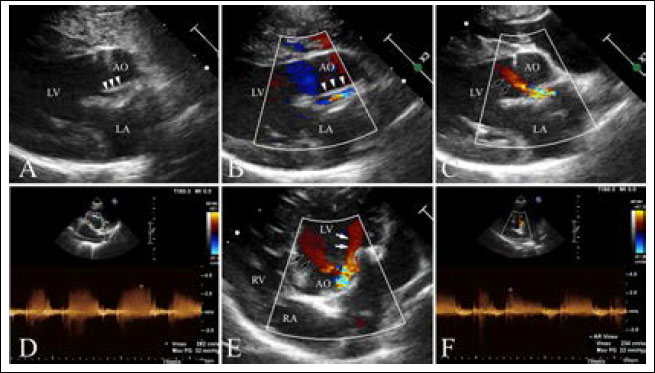

Transthoracic echocardiography (Affiniti 50; Philips Medical Systems, WA, USA) was performed with a sector-array transducer (4–12 MHz). An abnormal slit-like tunnel structure, 2.2 mm in internal diameter, connecting the ascending aorta to the left ventricle was detected above the sinutubular junction. The opening of this structure was located in the base of the ventriculoaortic junction between the anterior mitral leaflet and non-coronary cusp. The morphology and motion of both the mitral and arterial valves were normal, with no evidence of aortic stenosis, mitral regurgitation, or valvular vegetation (Supplementary video I). During the diastolic phase, a regurgitant jet was detected along the aortic cusps with a 2.8 m/second peak velocity and 32 mmHg pressure gradient and along the anterior mitral leaflet with a 2.3 m/second peak velocity and 22 mmHg pressure gradient from the tunnel opening to the left ventricle (Fig. 2, Supplementary Video I). There was mild left ventricular eccentric hypertrophy with an internal diameter in diastole and systole of 23.7 mm (reference range: 16.70–18.93 mm) and 12.2 mm (reference range: 9.04–10.98 mm), respectively. The normalized value of the end diastolic left ventricular interior dimension was 1.63 (reference range: <1.7). The interventricular septum thickness in diastole and systole was 4.9 mm (reference range: 5.70–7.53 mm) and 6.1 mm (reference range: 8.60–10.64 mm), respectively. The thickness of the left posterior wall during diastole and systole was 4.6 mm (reference range: 4.53–6.03 mm) and 7.0 mm (reference range: 7.97–9.55 mm), respectively. Left ventricular systolic function was normal based on fractional shortening of 48.5% and an ejection fraction of 61.6% obtained by Simpson’s method of discs.

Fig. 2. Echocardiography of right parasternal five chamber view (A–C), oblique right parasternal short axis view of the heart base (D), and oblique left apical long axis view (E,F). (A, B) an abnormal slit-like tunnel structure (arrowheads) next to the aorta is shown. (A,C) The opening of this tunnel structure is located in the base of the ventriculoaortic junction between the non-coronary cusps and anterior mitral leaflet. (D–F) during the diastolic phase, a regurgitant jet is detected along the aortic cusps (black arrows; 2.8 m/second peak velocity, 32 mmHg pressure gradient) and along the anterior mitral leaflet (white arrows; 2.3 m/second peak velocity, 22 mmHg pressure gradient) from the tunnel opening to the left ventricle.